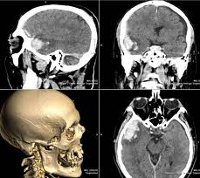

КТ черепа

Исследование излучения позволяет исследовать кости черепов мозга и лица, челюстей и лобных пазух, оценить целостность и симметрию твердых структур, выявить расхождение швов, определить размер и форму полостей. КТ черепа можно использовать при черепно-мозговой травме. Методика позволяет установить наличие, положение и характер перелома, подтвердить повреждение вещества мозга. Используя процедуру, они определяют причины ликвореи в случае перелома основания черепа, диагностируют патологию височной кости с возможным повреждением слухового аппарата, искривление перегородки носа, локализацию соответствующих зубов. Процедура показана для выявления опухолей костей черепа и околоносовых пазух (в том числе при росте опухолей из соседних областей), метастазов, полипов, кист. Техника предписана для исключения большего количества костных повреждений при фиброзной дисплазии, которая может протекать бессимптомно на ранних стадиях.

При использовании метода структуры мягких тканей видны хуже, чем кости, поэтому для их исследования иногда используют компьютерную томографию с контрастированием. Процедура проводится при ушибах, отеках лица и шеи, гематомах, воспалительных процессах, опухолях мягких тканей. В качестве показаний можно считать тяжелое течение лобного синусита, синусит при подозрении на распространение за пазухой с поражением мягких тканей и твердых структур. Кроме того, сканирование выполняется перед сложными реконструктивными операциями, чтобы заранее спланировать ход хирургического вмешательства (особенно пластики) и в послеоперационный период, чтобы оценить результаты операции.

Преимуществами исследования являются возможность одновременно исследовать все структуры черепа, создавать трехмерные изображения на основе многократного сканирования, печатать изображения или сохранять их в электронном виде. Недостатками метода являются использование рентгенограмм и накопление дозы облучения с возможным превышением стандартов при очень частых исследованиях (процедура радиационной нагрузки составляет 2-3 мЗв, что ниже допустимой нормы). Кроме того, у некоторых пациентов возникают аллергические реакции на контраст. Альтернативой КТ (в зависимости от характера предполагаемой патологии) являются обычная рентгенография и магнитно-резонансная томография.